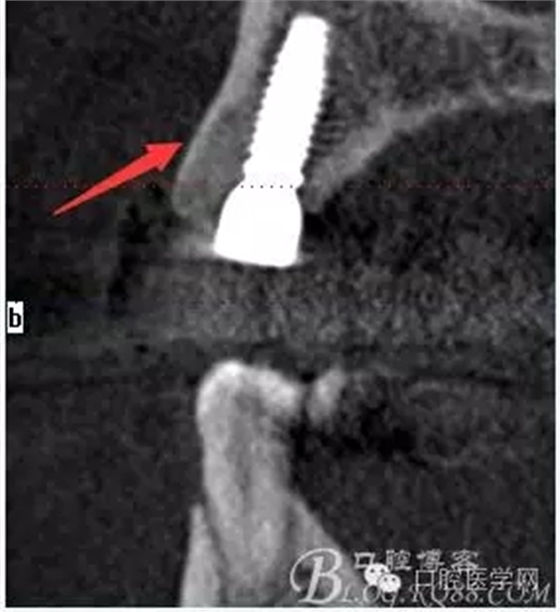

植入當(dāng)然毫無難度可言,只是想術(shù)后的方向更加賞心悅目而已,14稍微有點難度,記住 上頜牙顎側(cè)骨板肯定比頰側(cè)硬多了。 所以(特別是柱行種植體柱行鉆)永遠(yuǎn)要記住上頜牙備洞過程是會往頰側(cè)慢慢偏出去的 。(根型植體菱形鉆相對這個問題好控制點)所以我們第一鉆定位要比預(yù)計的中心點更加靠顎側(cè)多點 ,到底多多少,這個很難把握,感覺吧 。 上圖我畫了小圈的地方,是種植體離頰側(cè)和近中骨壁的距離空腔 (這個情況可以考慮植骨或者不植骨 我選擇了自體骨)。

軟組織簡單處理以后 簡單縫合 植體三維空間非常理想

術(shù)后片顯示方向非??梢?p style="text-align:center">

頰顎向的方向也很理想 箭頭所示 空間填滿了自體骨